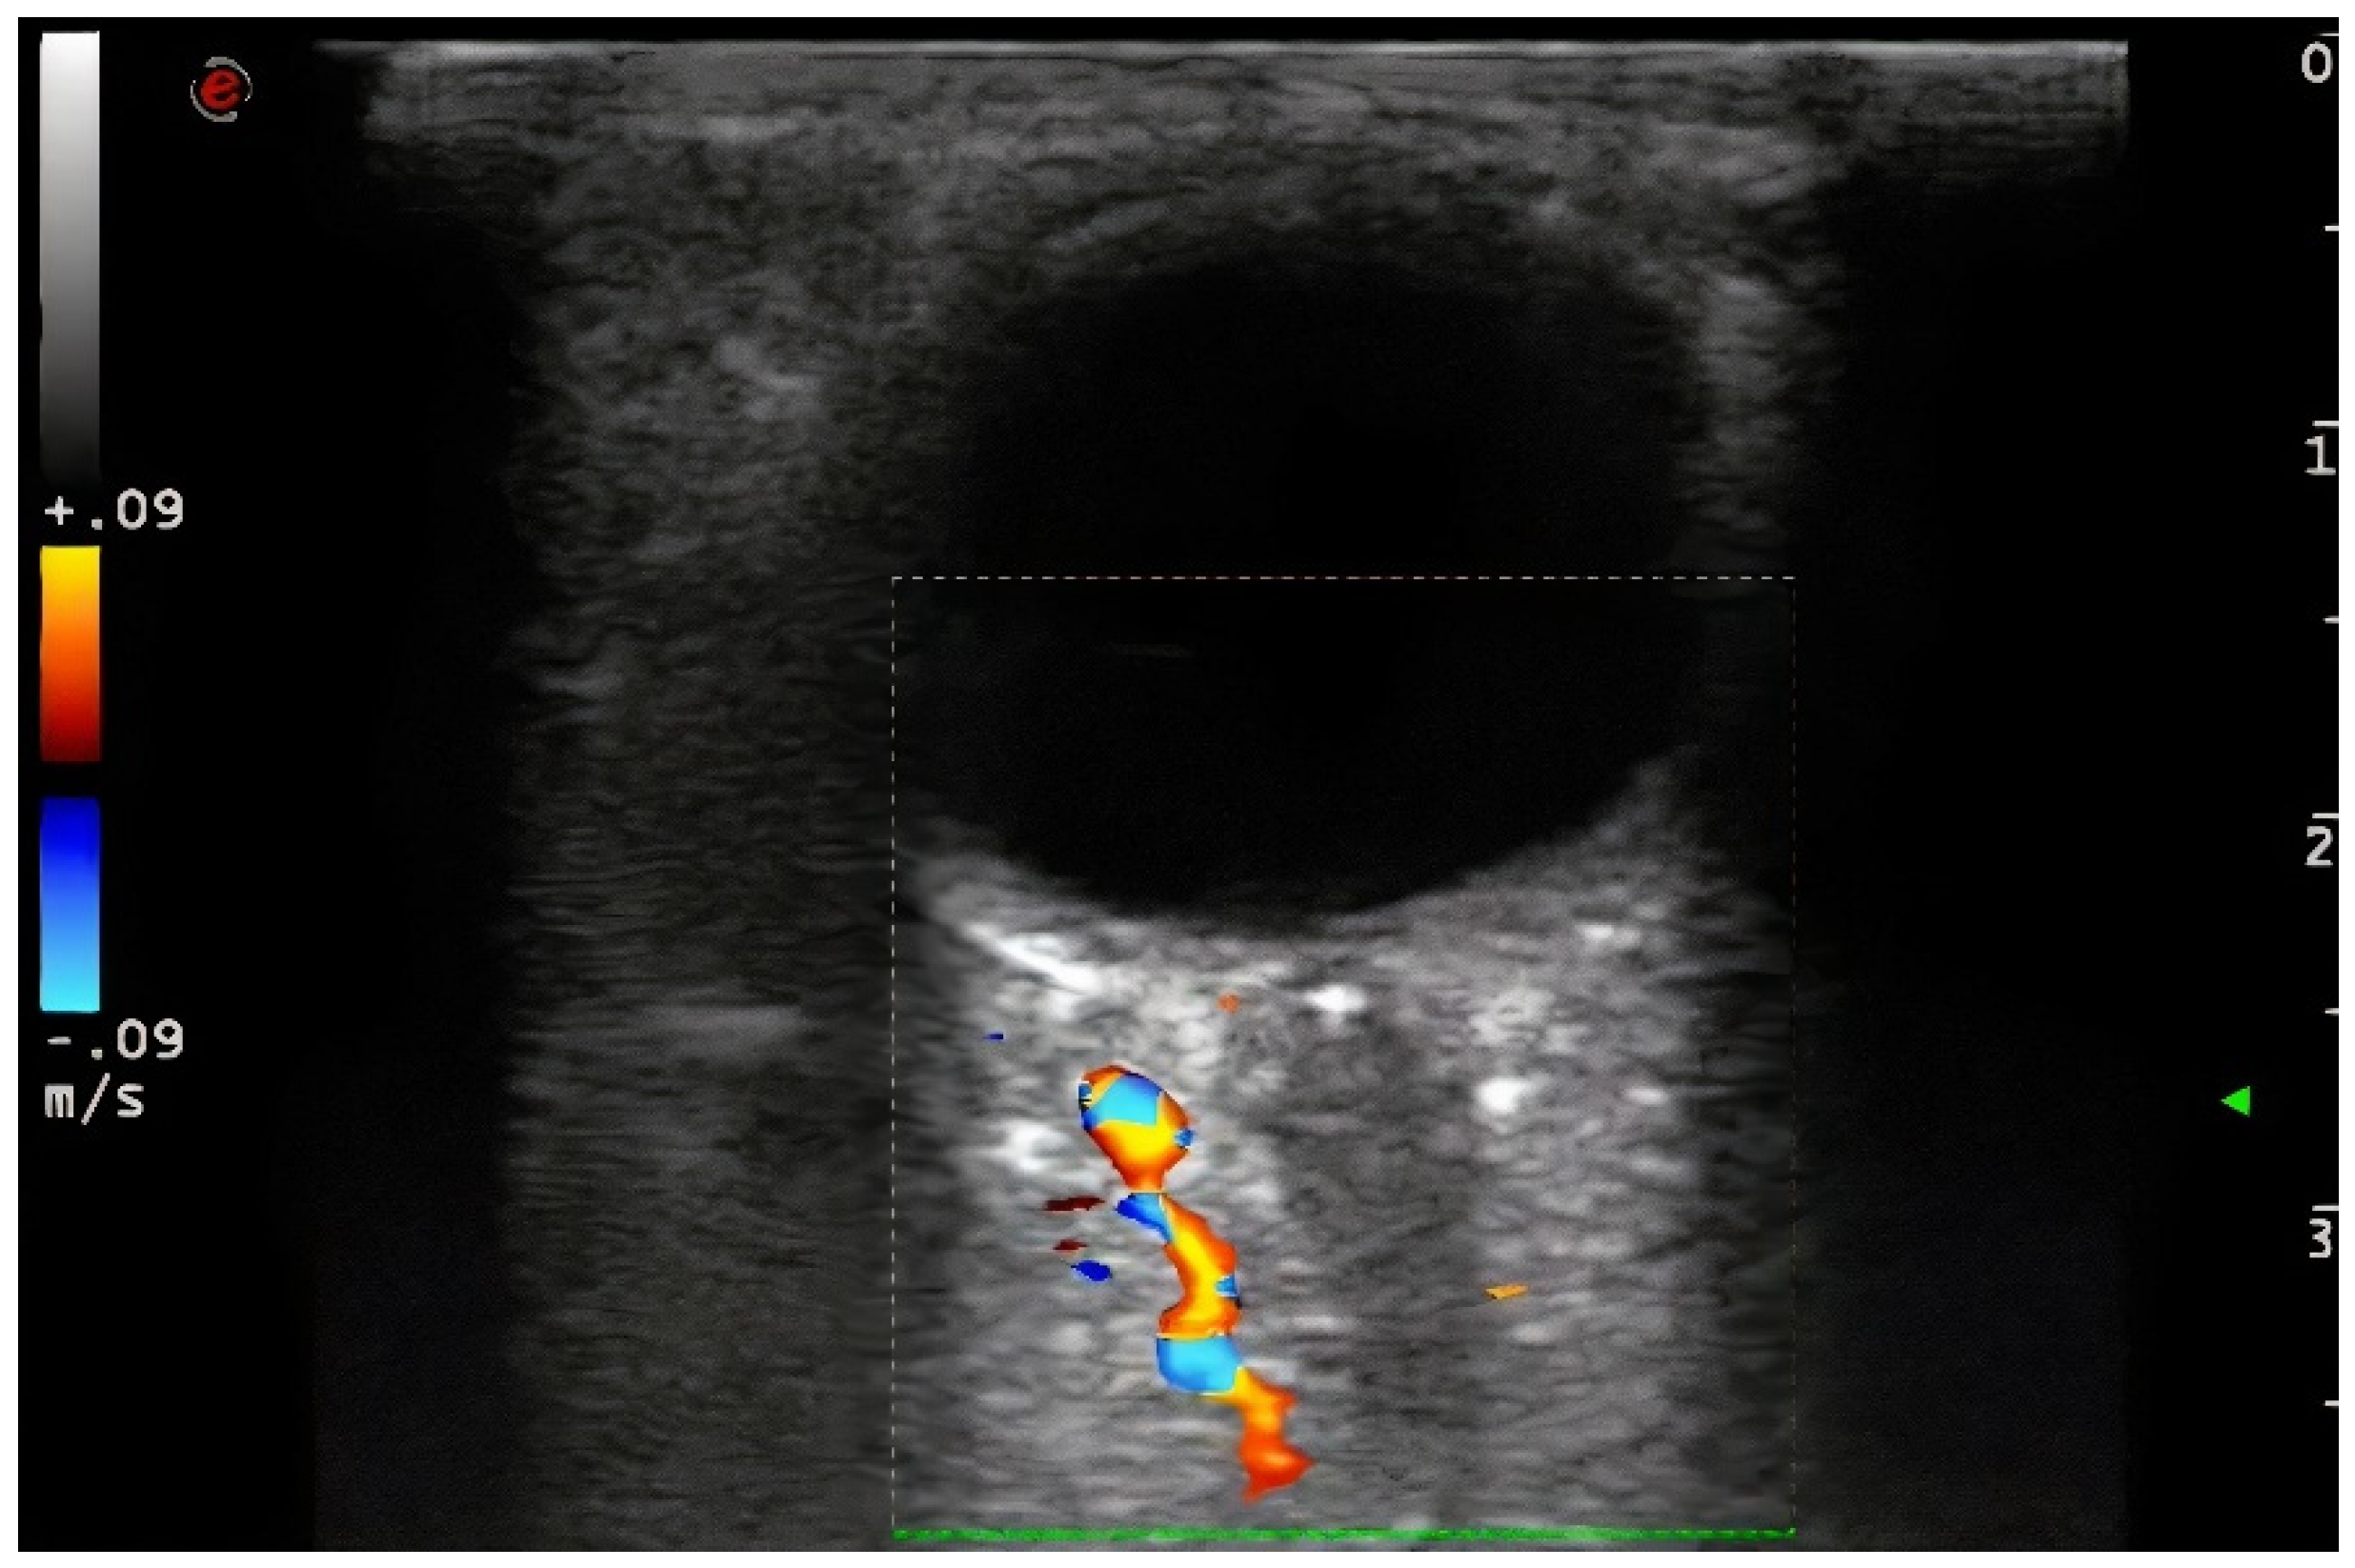

Demographic variables and vascular risk factors were collected. Orbital ultrasound findings were obtained using a 3–9 MHz linear probe (Esaote MyLab70 and My Lab9, Esaote, Milan): the absence of color and pulsed Doppler signal in the peripapillary portion of the CRA (diagnosis of CRAO) (Figure 1) and the presence of hyperechoic material in the retrobulbar circulation of the optic nerve (spot sign) were explored (Figure 2).

Figure 1. The absence of color and pulsed Doppler signal in the peripapillary portion of the CRA (diagnosis of CRAO). 3–9 MHz linear probe (Esaote MyLab70 and My Lab9, Esaote, Milan).